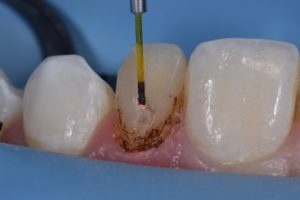

This case was referred to me for improvement of the esthetics of composite bonding on #7 and 10. A diagnostic wax-up was generated as the referring dentist required certain proportions relative to primary anatomy to be confirmed before starting. A decision was made to modify the gingival contour of 10 (diode, 810nm, 980nm, 1.0W SuperPulsed) (Gemini, Ultradent, UT), with bone sounding the basis for whether osseous recontouring was necessary. In this case, transsulcular osseous recontouring using a Wedelstaedt chisel (Kois) (Brasseler) was utilized to re-establish biologic width on the day of the restorations. Approximate full healing time: 3 months. Approximate “purple” look to gingiva: 2-3 weeks. Most of the old composite was removed except for areas where it could not easily be distinguished from tooth structure. After defining finish lines, the teeth were isolated with metal strips and micro air abraded (27 micron aluminum oxide) before a total etch approach. Silane coupling agent was utilized (GC G-MultiPrimer) before bonding (GC G-Premio Bond). A layered approach was utilized (4 separate layers) using shades XL1 Enamel, A1 Enamel, XL2 Dentin, Trans Clear from Kerr Harmonize.